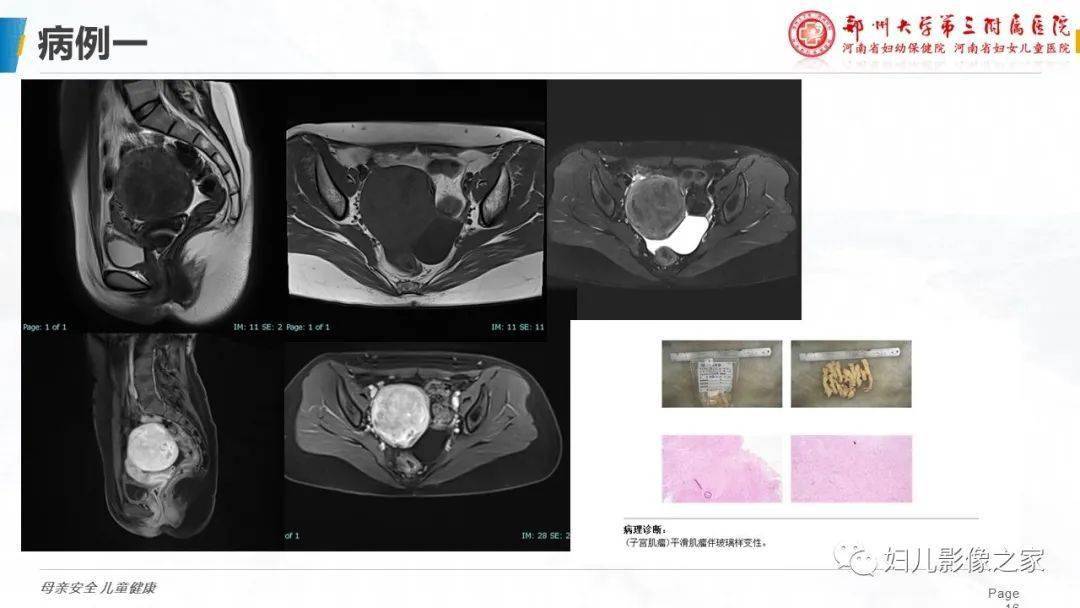

子宫平滑肌瘤变性的影像诊断